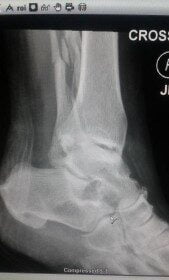

X-rays and Mom — Case Study into the State of Imaging Technology

Reposted from Imaging Technology News (ITN) with permission. Reposted from Imaging Technology News…